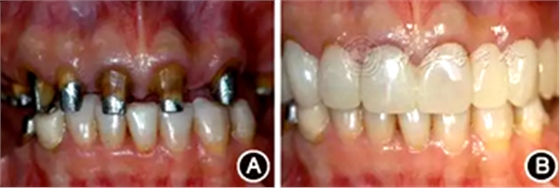

術(shù)后2周進行重新牙體預(yù)備,制作并戴入臨時修復(fù)體,牙齦塑形(圖6)。術(shù)后3個月,上前牙牙齦形、線、點位置基本穩(wěn)定,進行永久修復(fù)。上頜采用烤瓷固定橋修復(fù),樁核冠單冠修復(fù),下頜固定-活動義齒修復(fù),恢復(fù)良好的牙齒外形和接觸區(qū)、重建完整牙列、恢復(fù)口腔功能、改善美學(xué)效果(圖7)。

圖7 永久性修復(fù)后即刻 A:正面開微笑像;B:前牙像